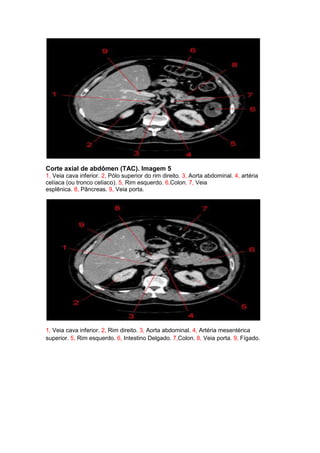

Corte axial de abdômen (TAC). Imagem 5

1, Veia cava inferior. 2, Pólo superior do rim direito. 3, Aorta abdominal. 4, artéria

celíaca (ou tronco celíaco). 5, Rim esquerdo. 6,Colon. 7, Veia

esplênica. 8, Pâncreas. 9, Veia porta.

1, Veia cava inferior. 2, Rim direito. 3, Aorta abdominal. 4, Artéria mesentérica

superior. 5, Rim esquerdo. 6, Intestino Delgado. 7,Colon. 8, Veia porta. 9, Fígado.

Corte axial deabdômen (TAC). Imagem 5 1, Veia cava inferior. 2, Pólo superior do rim direito. 3, Aorta abdominal. 4, artéria celíaca (ou tronco celíaco). 5, Rim esquerdo. 6,Colon. 7, Veia esplênica. 8, Pâncreas. 9, Veia porta. 1, Veia cava inferior. 2, Rim direito. 3, Aorta abdominal. 4, Artéria mesentérica superior. 5, Rim esquerdo. 6, Intestino Delgado. 7,Colon. 8, Veia porta. 9, Fígado.